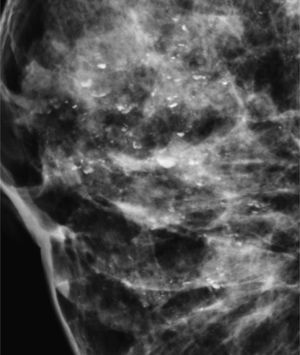

Las calcificaciones indeterminadas, como las demás, pueden ocupar una zona extensa de la mama (fig. 8), ser segmentarias (cuando ocupan un segmento) o estar agrupadas (fig. 9)6.